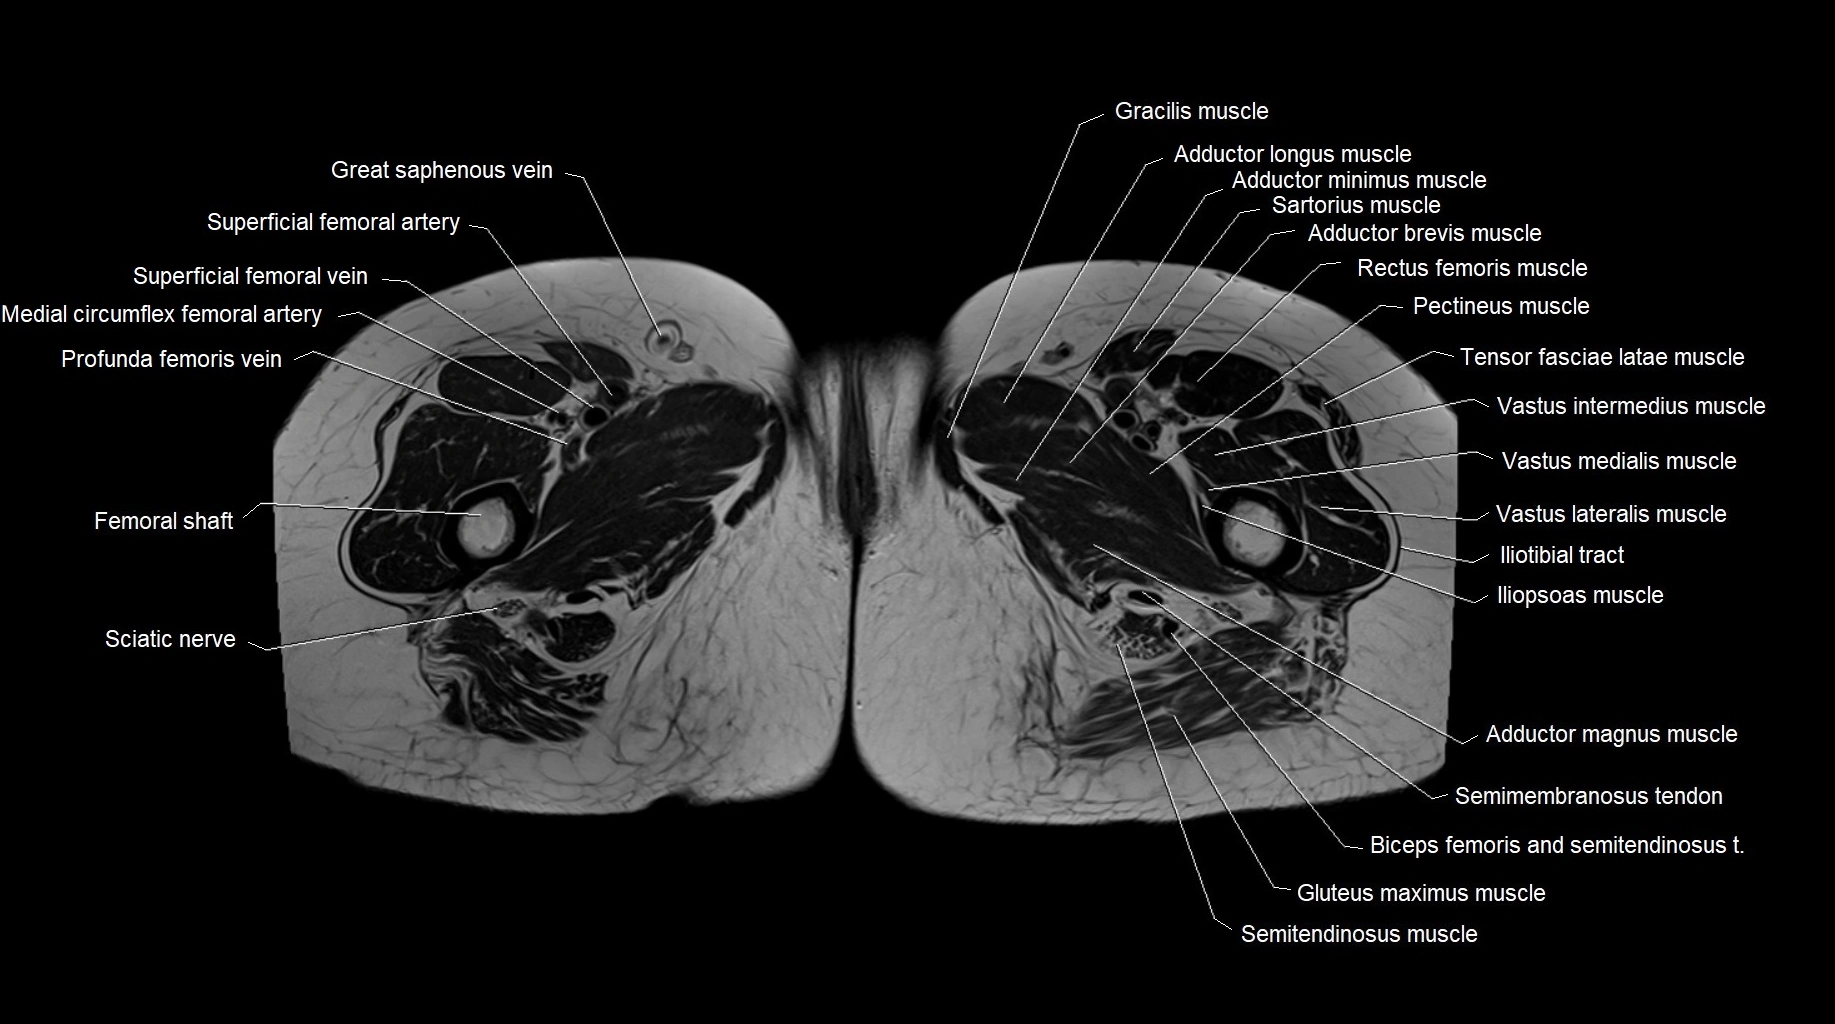

- Adductor brevis muscle

- Adductor longus muscle

- Adductor magnus muscle

- Adductor minimus muscle

- Femoral shaft

- Gracilis muscle

- Iliopsoas muscle

- Iliotibial tract

- Medial circumflex femoral artery

- Pectineus muscle

- Rectus femoris muscle

- Sartorius muscle

- Sciatic nerve

- Semimembranosus tendon (proximal)

- Superficial femoral artery

- Tensor fasciae latae muscle

- Vastus intermedius muscle

- Vastus lateralis muscle

- Vastus medialis muscle